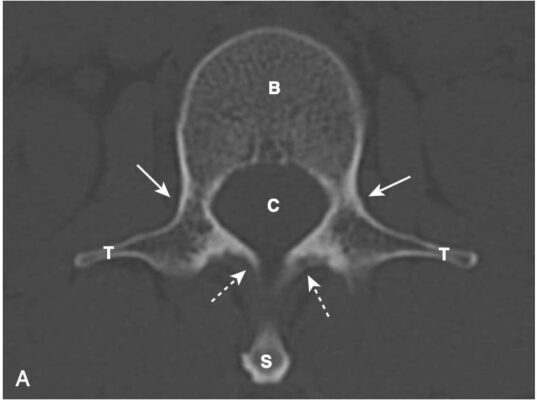

Mỗi đốt sống (hầu hết mọi đốt sống) đều có phần thân bao gồm xương xốp và tủy xương bên trong và phần sau được tạo bởi xương đặc, bao gồm cuống cung, bản cung, các diện khớp nhỏ (facet, mỏm khớp), mỏm ngang và mỏm gai (Hình 1, A).

- Trong hình chiếu thẳng, mỗi thân đốt sống hiển thị hai cuống cung hình oval có thể nhìn thấy được ở hai bên của thân đốt sống. Các cuống cung của L5 thường rất khó nhìn thấy ngay cả ở những người bình thường, bởi vì độ ưỡn của cột sống thắt lưng (xem Hình 1, B).